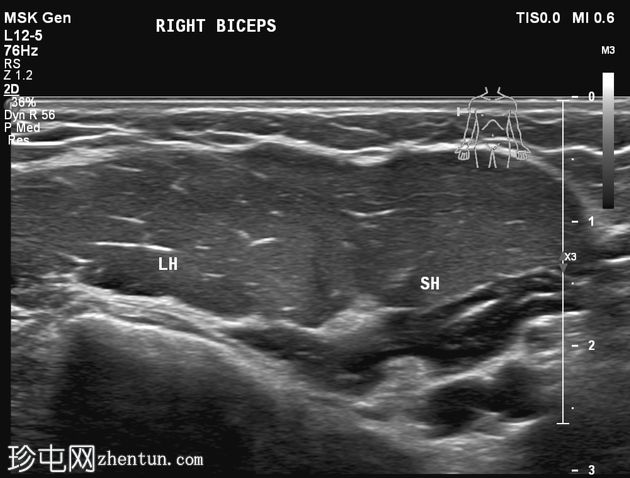

静息状态:肱二头肌短头和长头肌肉结构正常。肌腱和肌腱连接处完整,仅有轻微的断裂或积液迹象。

肘关节屈曲及肌肉收缩动态成像:肱二头肌短头和长头肌纤维之间出现充满液体的裂隙,提示局部肌筋膜分离/拉伤。未见肌纤维全层撕裂。肱二头肌远端止点正常。

诊断:肱二头肌短头和长头之间的动态肌筋膜损伤,收缩时裂隙内积液。

静息状态下的图像可能显示正常,这凸显了对有症状患​​者进行动态检查的重要性。